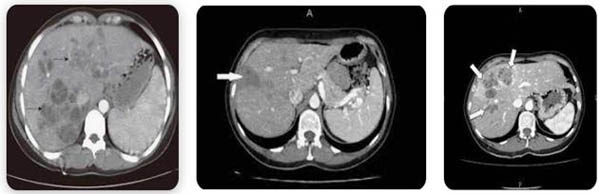

3. NỘI SOI MẬT TỤY NGƯỢC DÒNG (ERCP)

Thủ thuật nội soi mật tụy ngược dòng (Endoscopic Retrograde Cholangio-pancreatography) vừa có giá trị thăm dò, phát hiện, chẩn đoán, vừa có giá trị điều trị giải quyết trực tiếp sán Fasciolasp. kẹt trong hệ thống đường mật, nhất là trong pha/ giai đoạn sán lá nằm ở hệ đường mật thì thủ thuật này giúp lấy sán và cầm máu nếu có dấu xuất huyết đi kèm.

Hình 7. Áp dụng thủ thuật ERCP trong chẩn đoán và lấy sán ra đường mật tụy

Hình 8. Áp dụng thủ thuật ERCP trong chẩn đoán và lấy sán ra đường mật tụy

Nhiều trường hợp áp dụng ERCP và các can thiệp khacshuts cả dịch tá tràng, một ít dịch mật xét nghiệm thấy trứng sán bên trong